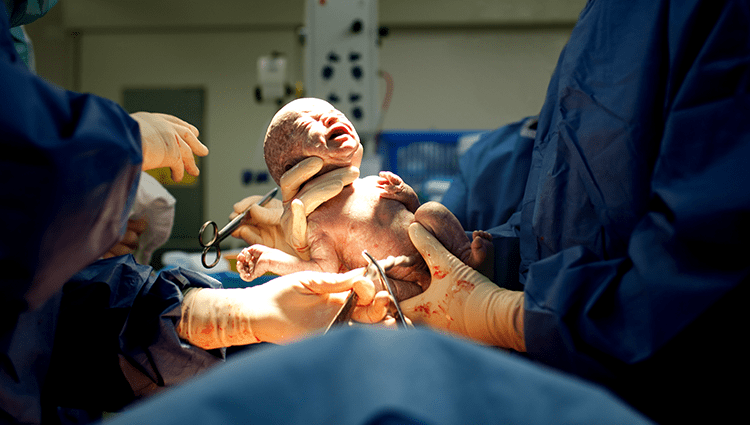

Obstetric & Gynaecological Surgery

- Mothers requiring safe obstetric interventions